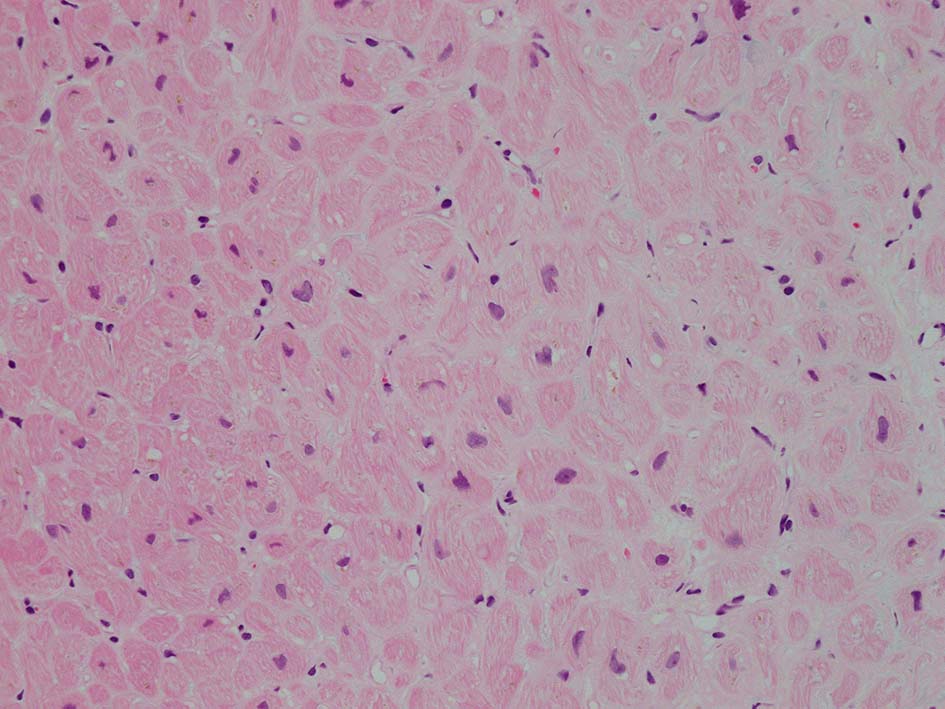

HE所見では, 明瞭な沈着物はわかりにくい. 血管壁が確認できる血管も少ない. congo-red染色で沈着が考えられる所見があり, 簡易偏光で(みずらいけれど)apple-greenの偏光があるように見える.(サムネイルのクリックで大きな画像が見られます)

心アミロイドーシス transthyretin type amyloidosis